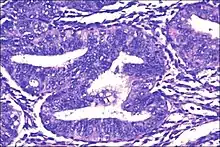

Histopathology of complex hyperplasia with atypia: Closely packed endometrial glands with sparse intervening stroma and stratification of the lining epithelium. Epithelial cells show cytological atypia with high nucleocytoplasmic ratio, irregular clumping of nuclear chromatin, and mitotic figures.[2]

• Atypical endometrial hyperplasia (simple or complex) - Simple or complex architectural changes, with worrisome (atypical) changes in gland cells, including cell stratification, tufting, loss of nuclear polarity, enlarged nuclei, and an increase in mitotic activity. These changes are similar to those seen in true cancer cells, but atypical hyperplasia does not show invasion into the connective tissues, the defining characteristic of cancer. The previously mentioned study found that 22% of patients with atypical hyperplasia eventually developed cancer.[6]